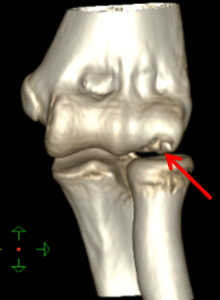

・CT検査:分離した骨の状態、遊離体の有無や位置の確認などを

・上腕骨小頭離断性骨軟骨炎

後方型

・後方インピンジメント障害

・尺骨肘頭疲労骨折

・肘頭骨端線損傷

・肘頭骨端線閉鎖不全